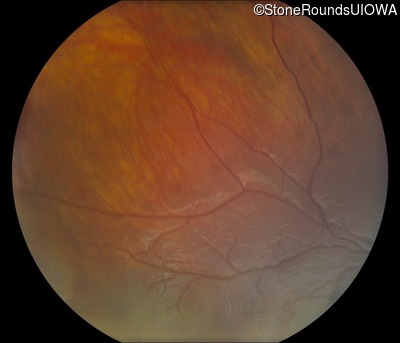

Fundus Photography - Right - 20/63 -2

Exemplar

Fundus Photography - Left - 20/50 -2